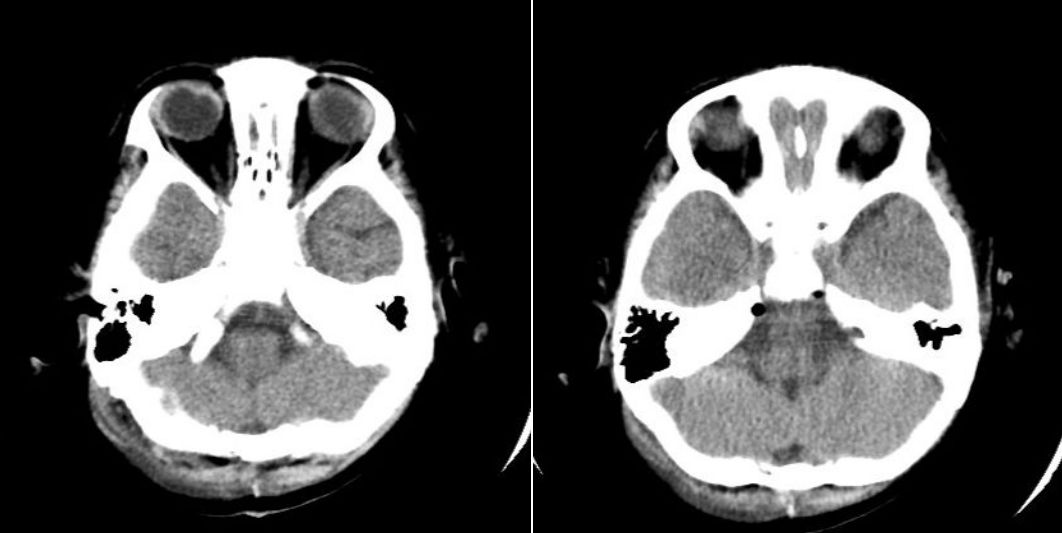

术后第二天顺利脱机,复查头颅CT仅见颅内少许积气,无颅内出血征象(图5)。